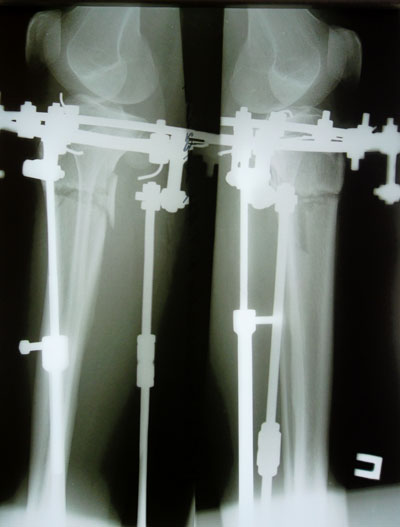

Дата операции 01.07.2014г.

Дата снятия аппаратов 17.10.2014г.

Срок лечения 97 дней.